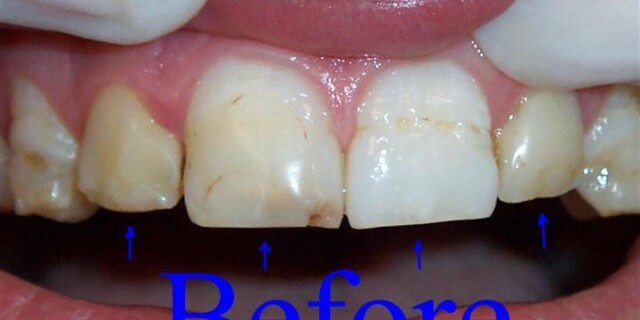

Cosmetic Dentistry

Ready to restore beauty, brightness, and luminescence to your smile? Our cosmetic dentistry services are designed to do just that! Our staff will work with you to determine which treatments best fit your needs and goals for your smile.